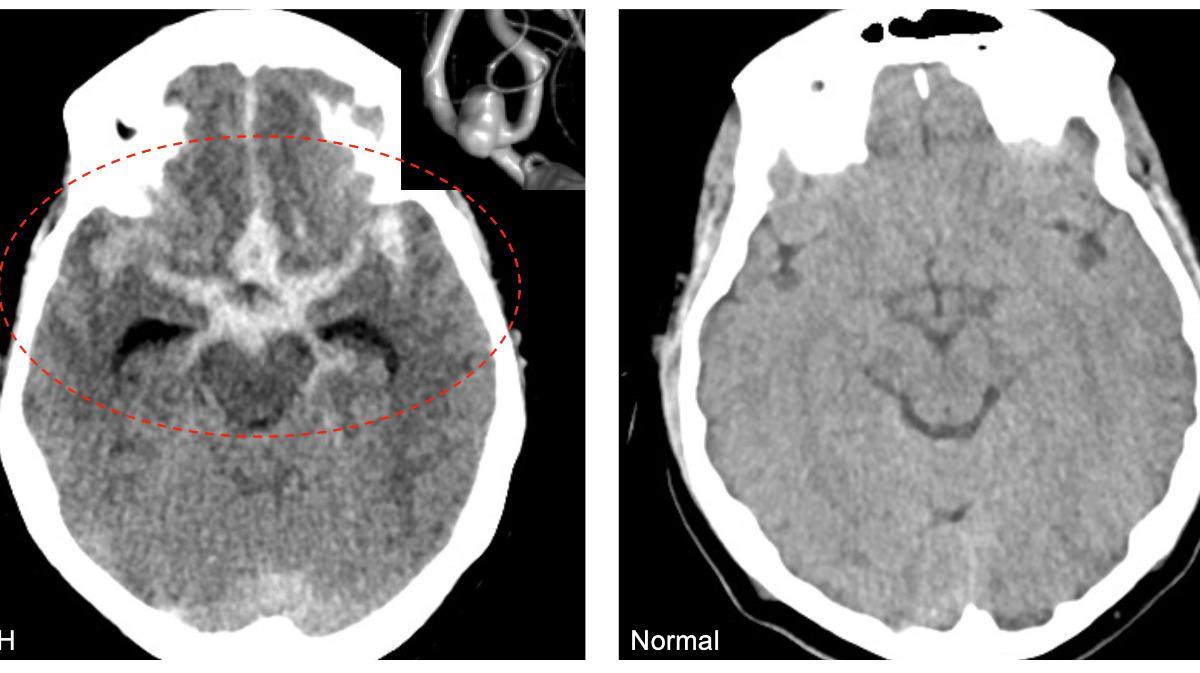

El círculo de la izquierda muestra una hemorragia subaracnoidea aneurismática (aSAH) o sangrado dentro del cerebro. A la derecha, un cerebro normal. / Crédito: Robert Rennert.

La exposición crónica a partículas finas en el aire (PM2.5) supera fronteras invisibles y afecta la salud neurológica. Investigaciones recientes han vinculado estos contaminantes con un aumento en la incidencia de hemorragia subaracnoidea aneurismática (aSAH), una forma de accidente cerebrovascular hemorrágico con tasa de mortalidad superior al 35% y secuelas graves en sobrevivientes.

Estudios previos han asociado la contaminación del aire con infartos isquémicos y hemorragias intracerebrales, pero la relación con la ruptura de aneurismas no había alcanzado evidencia estadística significativa hasta el momento. Ahora, un equipo encabezado por el Dr. Robert Rennert, en la Universidad de Utah, en Estados Unidos, estudió a 70 pacientes con aSAH entre 2018 y 2023.